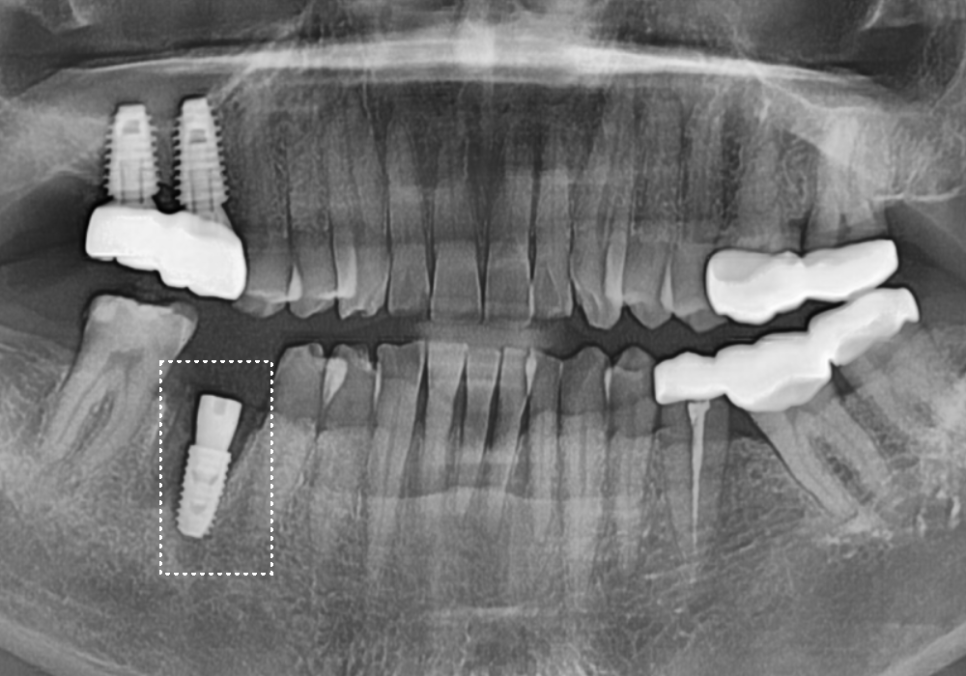

정확한 상태를 확인하기 위해

방사선 사진과 CT를 확인해 보았습니다.

역시나 뿌리 끝에 염증이 광범위하게 퍼져

까맣게 뼈가 녹아있는 모습을 볼 수 있었는데요...

안타깝지만 치아를 지탱할 뼈가

이미 상당 부분 소실되어

더는 살려 쓰기 어려운 단계였습니다.